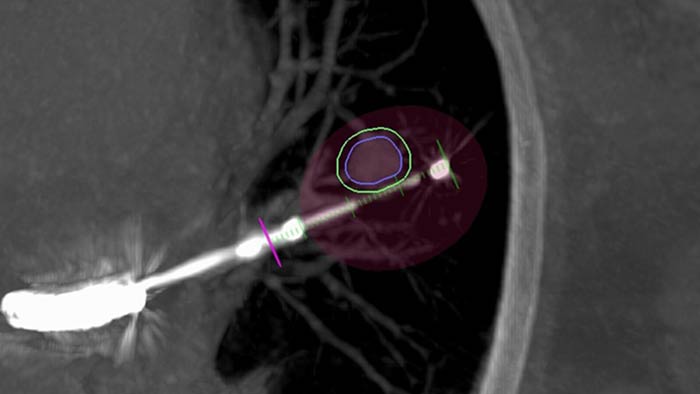

Low-dose high-quality imaging technology

ClarityIQ technology provides high-quality imaging for a variety of clinical procedures. It delivers excellent visibility at low X-ray dose levels for patients of all sizes. Multiple clinical studies on more than 19000 patients have been published on ClarityIQ technology to date revealing one truth: significantly lower dose across clinical areas, patients and operators.